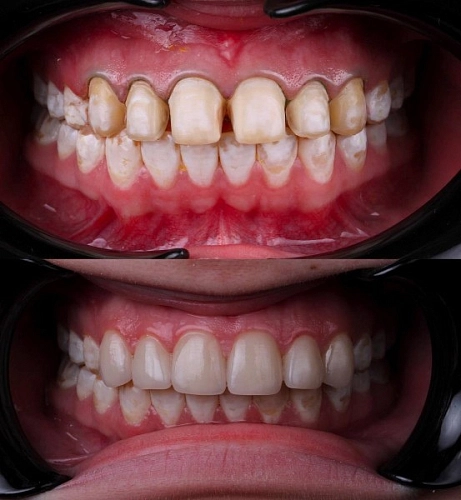

Как вылечить флюороз: ⠀

На начальном этапе проводится отбеливание, а затем назначается курс реминерализации. Возможно назначение медикаментов.⠀

При поражениях средней и тяжелой степени восстановить эмаль естественным образом уже невозможно. Вернуть зубам эстетичный вид можно при помощи композитных материалов, керамических виниров или коронок.⠀

На фото работа врача стоматолога - ортопеда Сергеевой Анастасии Сергеевной.